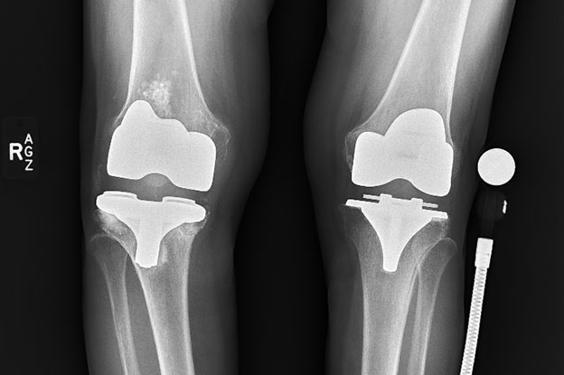

The patient was an 86-year-old woman who was the primary caregiver for her husband and had previously been an active person in the local community. She was experiencing increasing right knee pain and deformity and was unable to walk without the use of a cane. Even mundane daily activities were considerably more challenging as a result of her right knee pain and swelling.

A physical examination revealed anteroposterior and medial instability with 10-degree hyperextension to 90-degree flexion. Due to gross component loosening on radiographs and functional limitations, a revision knee procedure was planned.